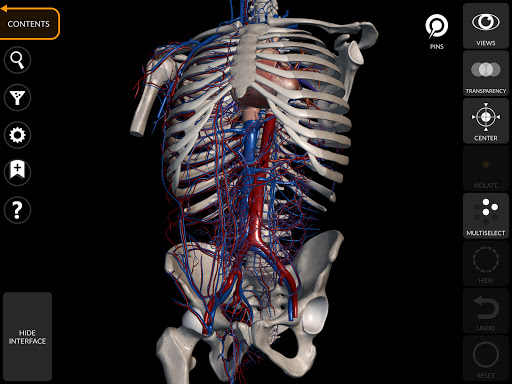

"Anatomy 3D Atlas" vous permet d'étudier l'anatomie humaine de manière simple et interactive.

Grâce à une interface simple et intuitive, il est possible d'observer chaque structure anatomique sous n'importe quel angle.

Les modèles anatomiques 3D sont particulièrement détaillés et avec des textures jusqu'à une résolution de 4k.

La subdivision par régions et les vues prédéfinies facilitent l'observation et l'étude de parties individuelles ou de groupes de systèmes et les relations entre différents organes.

• Système cardiovasculaire

• Filtrez pour masquer ou afficher chaque système

• Fonction de transparence